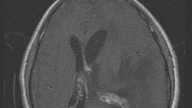

The first question to ask is where exactly is the tumor located within the spinal canal. The broad categories are: intramedullary, intradural-extramedullary, and extradural. An intramedullary mass will be centered within the substance of the spinal cord itself, which has been described as the claw sign. An intradural-extramedullary mass will form a meniscus with the cord and push it away. An extradural mass will be outside the thecal sac. Vertebral body or clear epidural involvement suggests an extradural location. In cases where the distinction is difficult, assess the cord above and below the mass.